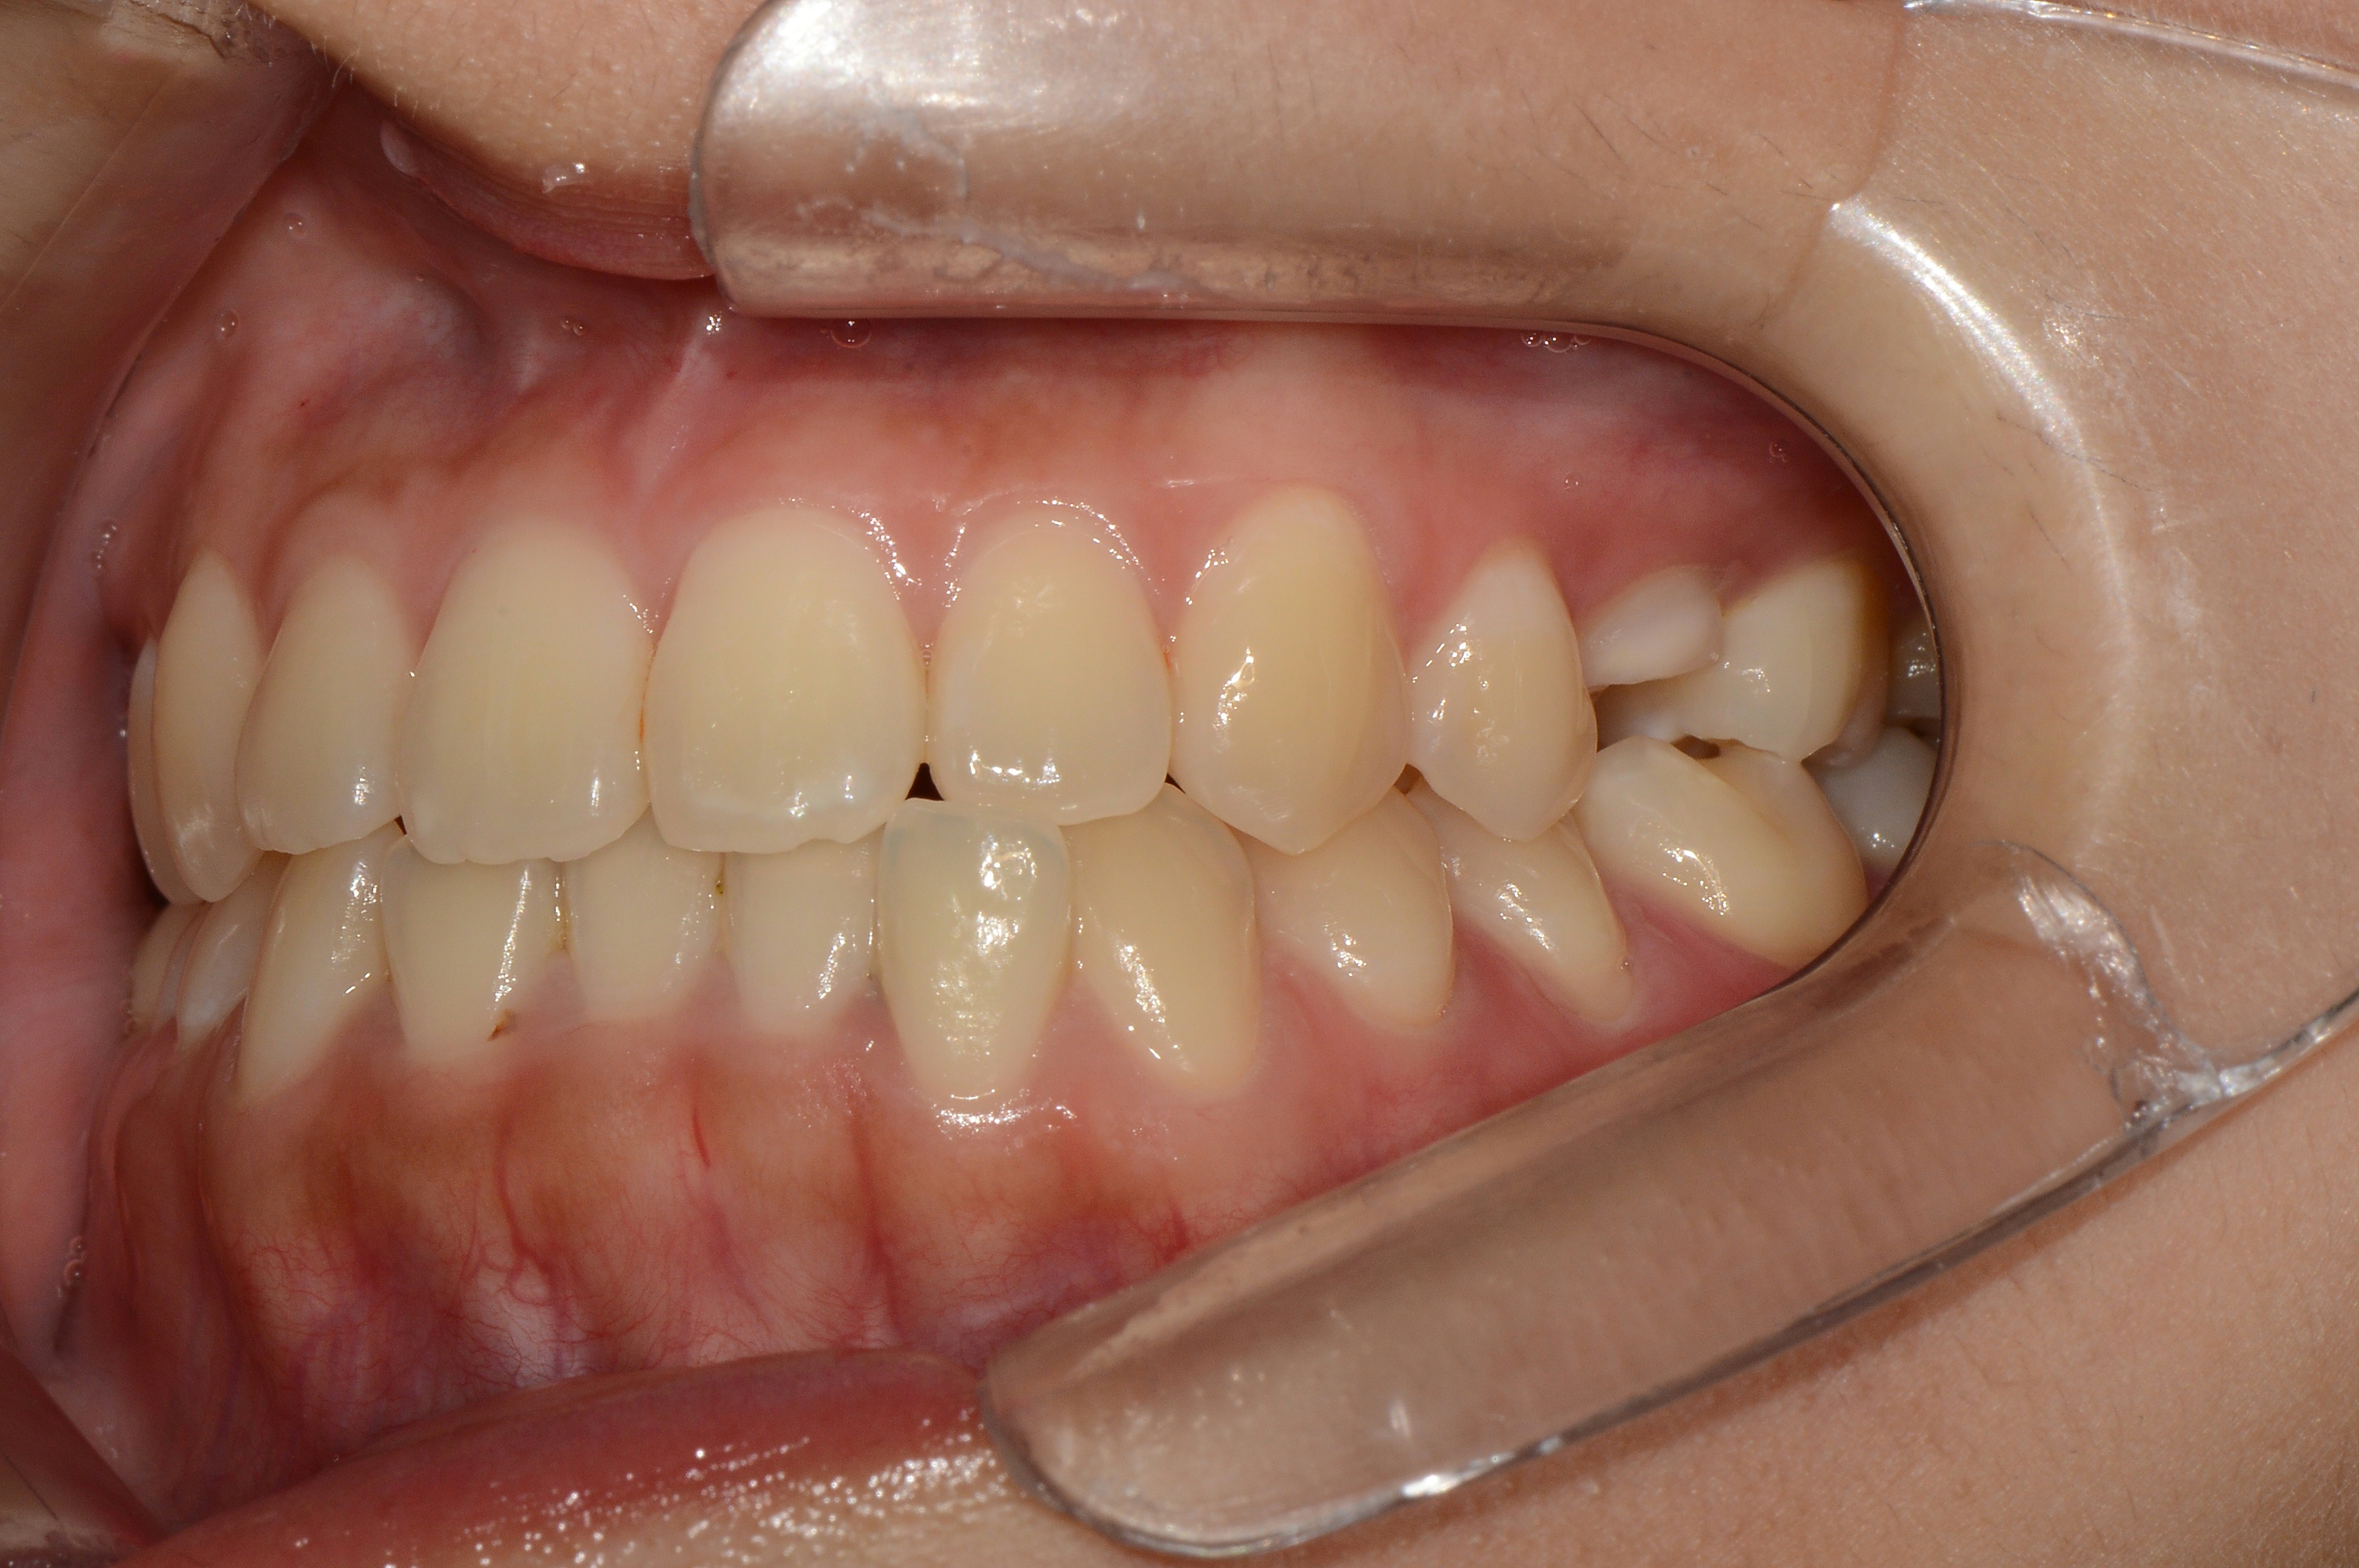

치료 전 사진입니다.